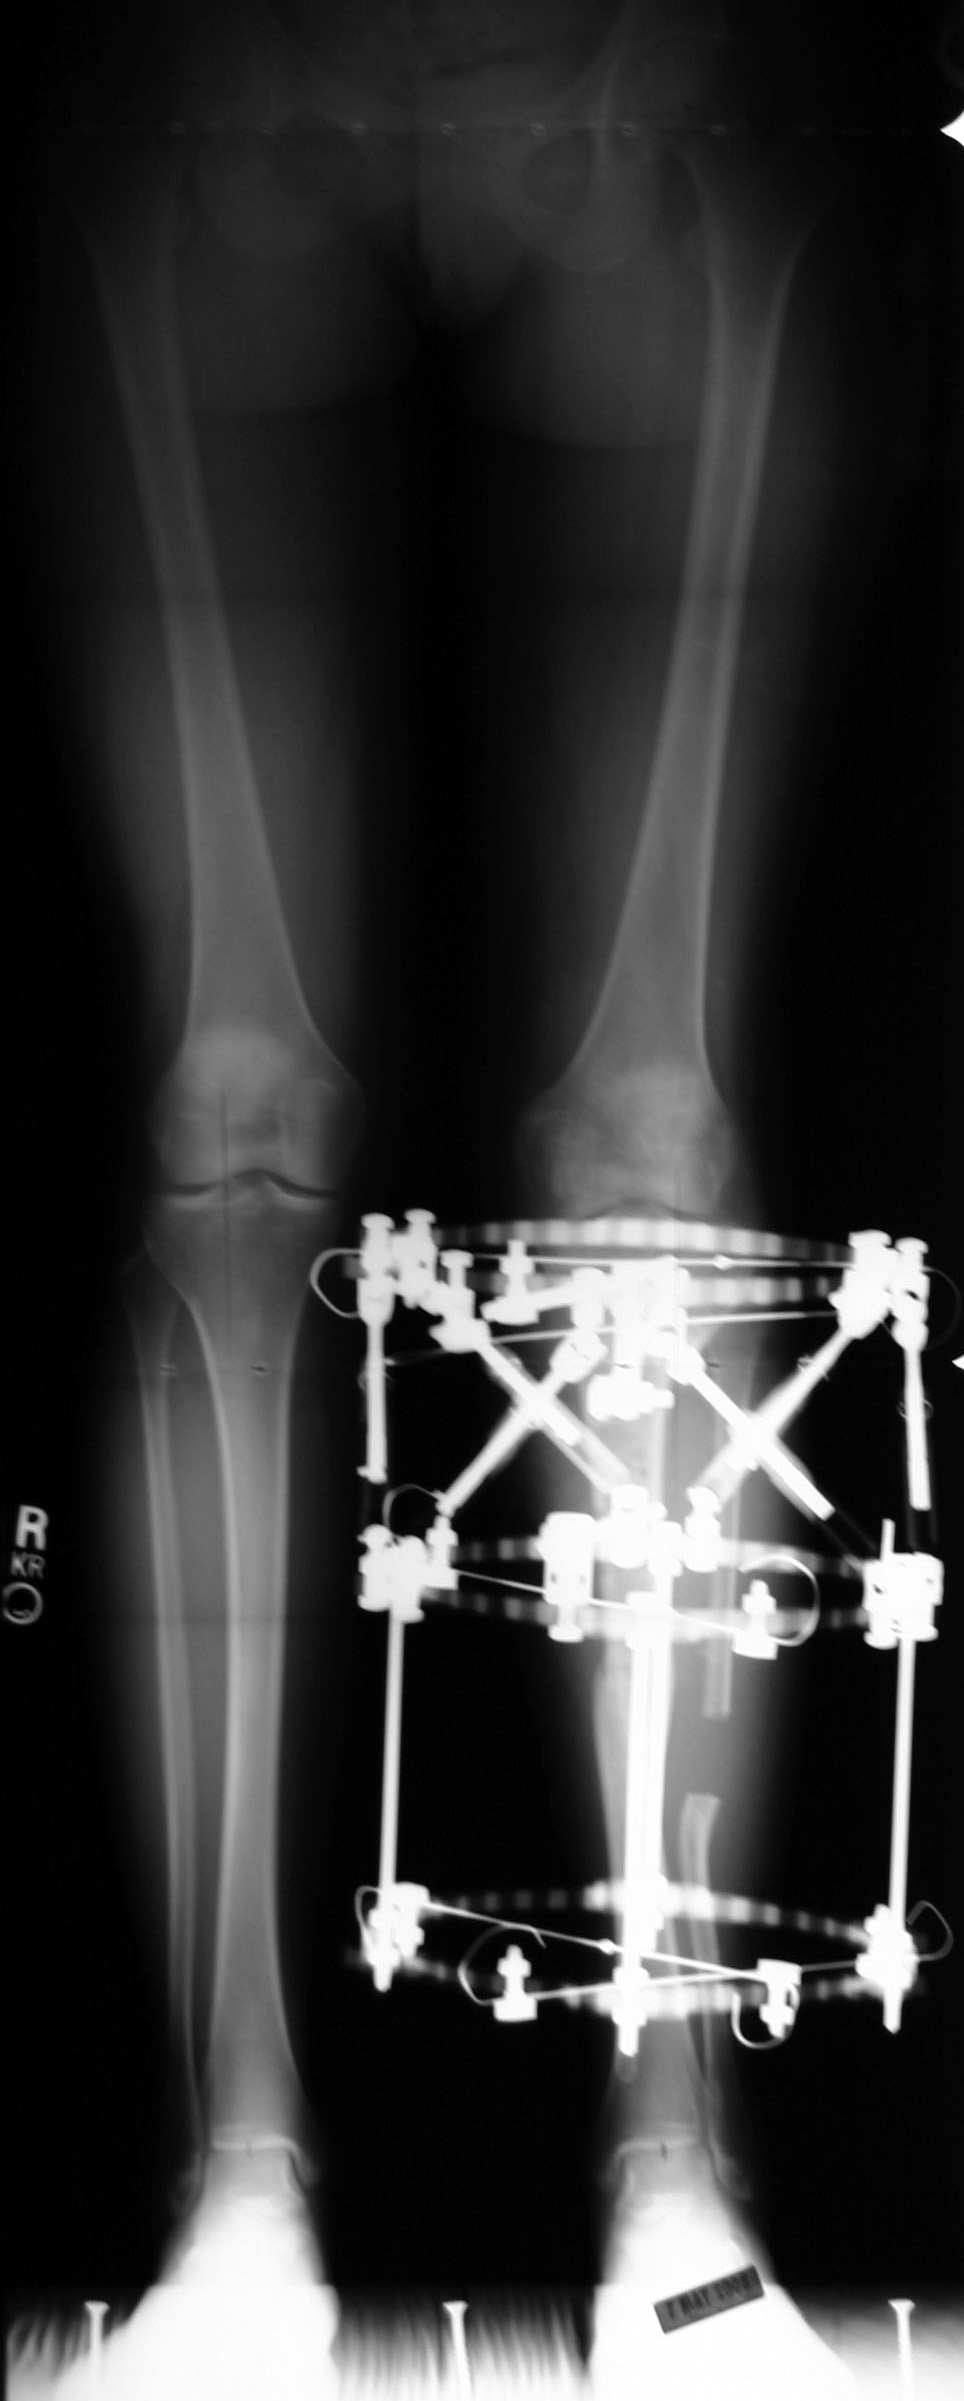

Deformities: Tibia Case 2

Result After Treatment by Dr. BrinkerFinal x-ray shows solid healing of the tibia and restoration of alignment of the limb. The patient now walks without assistance. |